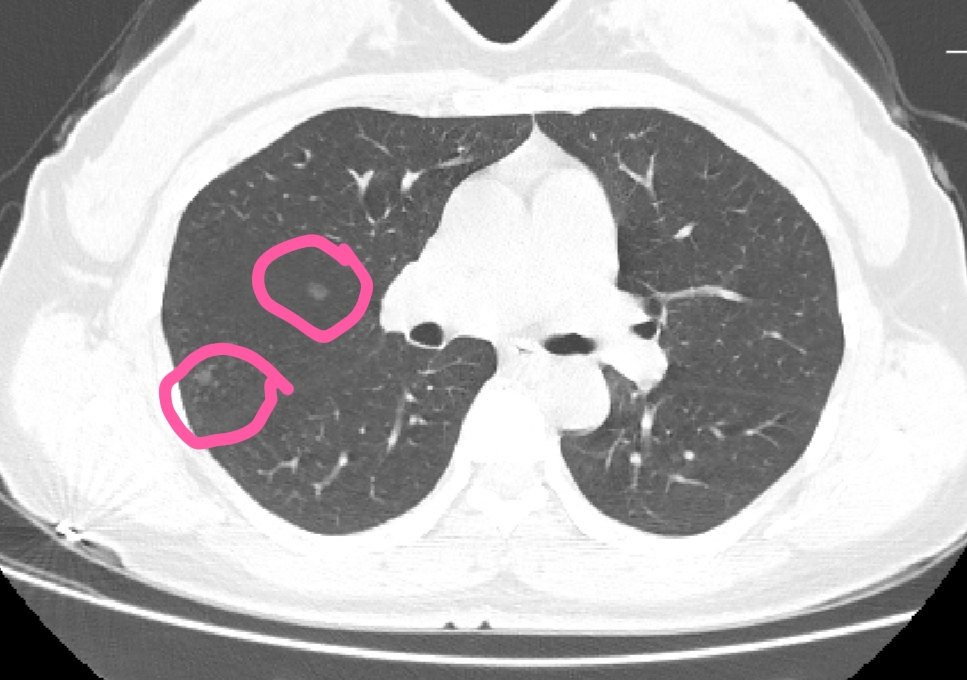

吸烟、长期粉尘接触,可在肺内发现多发结节,原因可能是吸入物质在肺内的沉积,也可能是长期慢性炎症所致;感染,较常见的是肺结核,结核杆菌感染导致肺渗出、增殖、钙化等一系列病理改变,在ct可表现为肺内结节;肺癌,影像学表现为肺中央或周围恶性的肺占位性病变,可见毛刺征、鼠尾征等,是肺内结节首先考虑及排除的诊断。

首先,明确病史,确定是否有吸烟、粉尘接触等病史,询问是否与咳嗽、咳痰、咯血、发热等症状,通过病史可以排除鉴别部分可导致肺内结节的疾病。其次,根据病史可以明确完需要完善的检查,比如说,有咳嗽咳痰者完善血常规及炎症指标,可以确定是否有感染;有长期吸烟或粉尘接触可完善胸部ct、肺功能检查等确定病变性质,肺实质还是间质,是否和气道狭窄有关。

事实上,随着预防医学的观念深入人心,定期体检的重要性的普及,检查肺内结节越来越常见,需进一步确定结节性质及位置,定性、定位准确后采取对应的治疗手段,感染者接受抗感染治疗,结核则采取抗结核治疗,若是恶性,则根据结节大小、位置及恶性程度选择合适的术式。